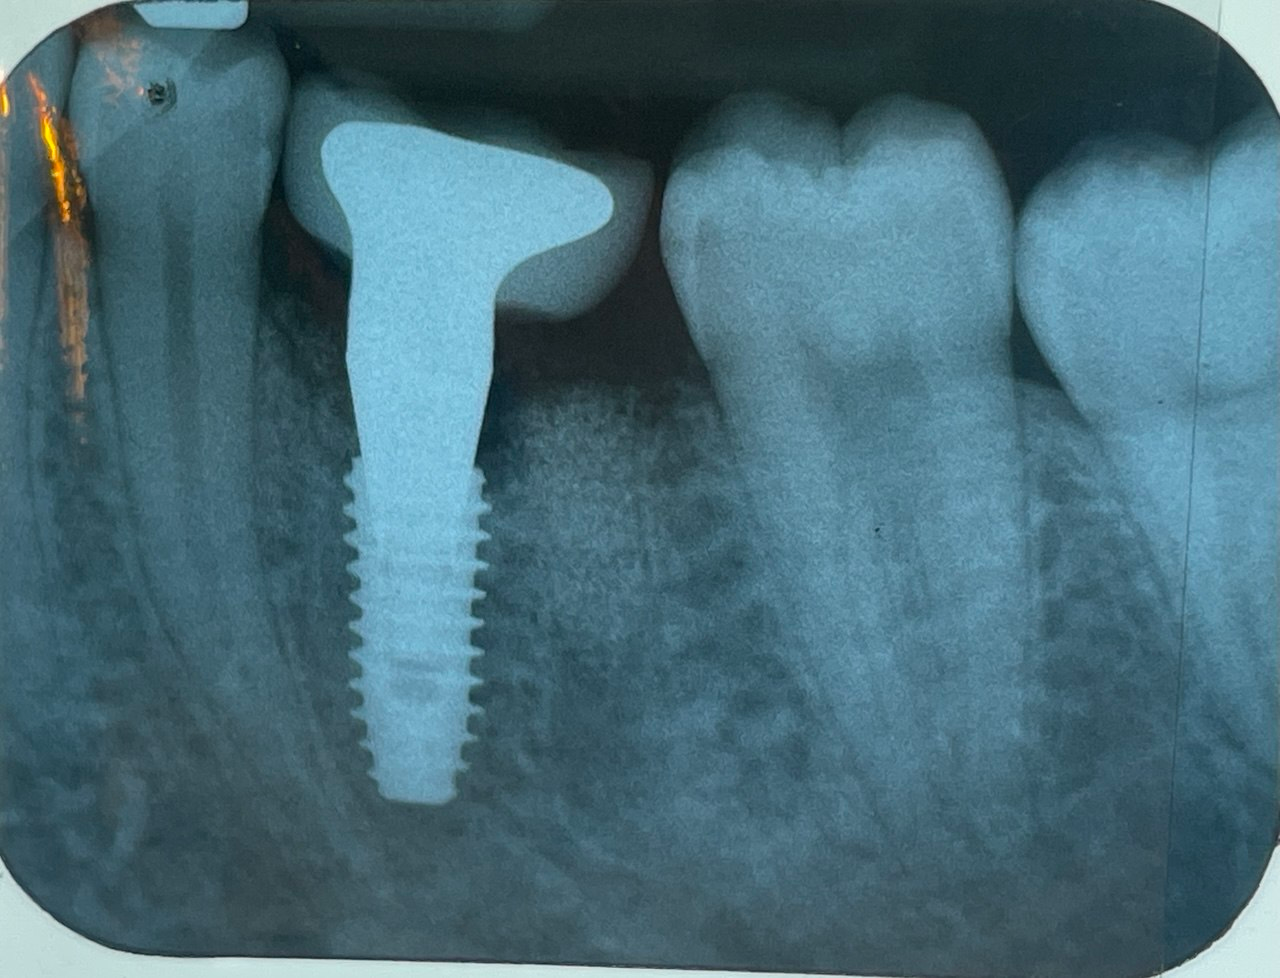

2. What option can be selected regarding the implant seen in this X ray?